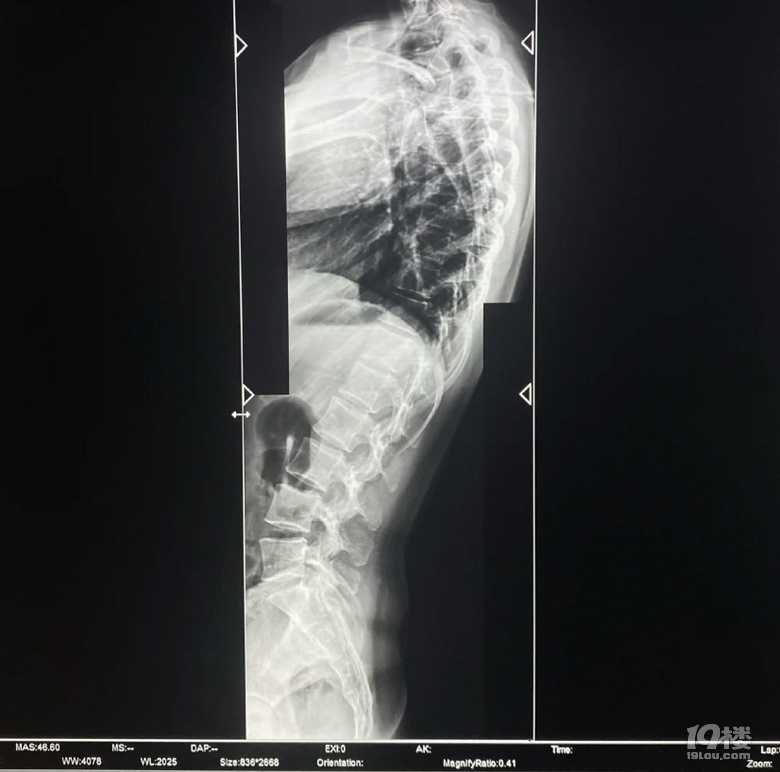

疼得有點(diǎn)熬不住了,上周去骨科掛號,醫(yī)生讓我拍一個全脊柱X正側(cè)位片,果然彎了……大概二十度,不用做手術(shù),當(dāng)時我還在竊喜,省了十多萬的手術(shù)費(fèi),結(jié)果醫(yī)生跟我說了一個更嚴(yán)重的問題,我的頸椎變直了!醫(yī)生說看我頸紋也很明顯,沒少低頭玩手機(jī)吧?我這個年紀(jì)不應(yīng)該是這樣的頸椎,六七十歲的人才會這樣。